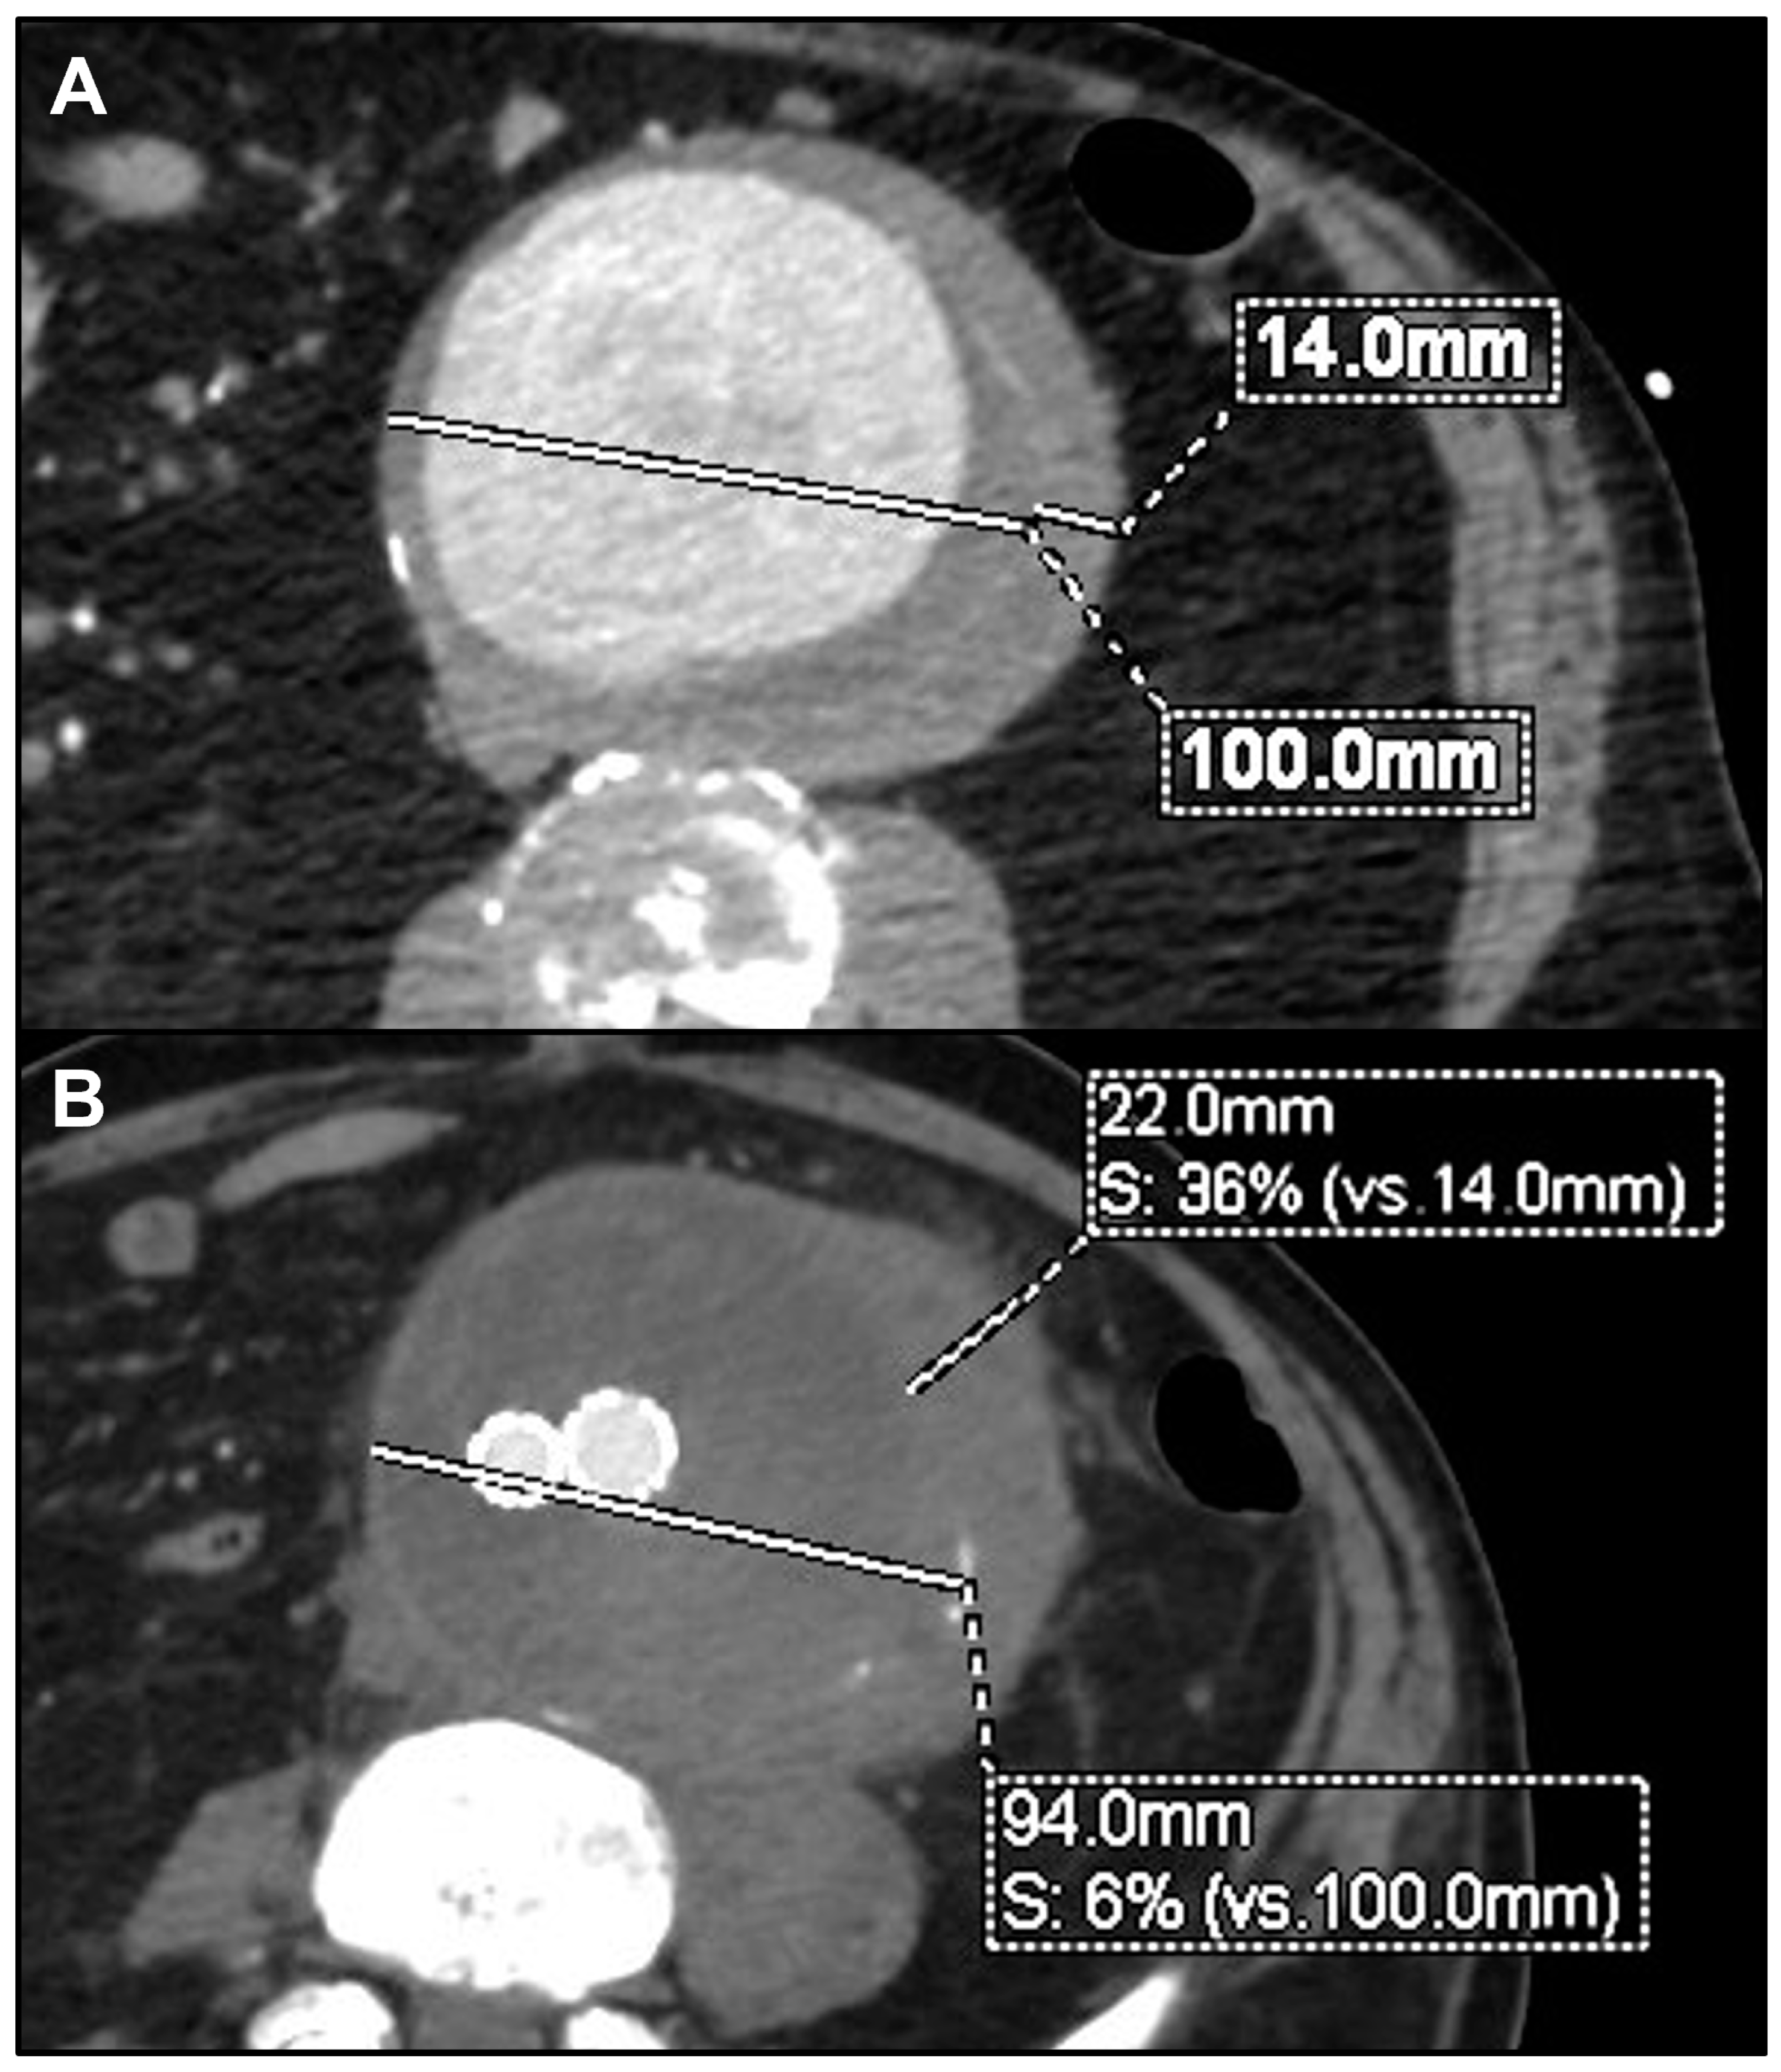

| 1 | M | 85 | Endocarditis | Staphylococcus aureus | Yes | Symptomatic rapidly growing thoracic PAU | Oxacyllin | TEVAR | Alive | 48 | Proximal disease progression | Redo TEVAR ± LSA embolization |